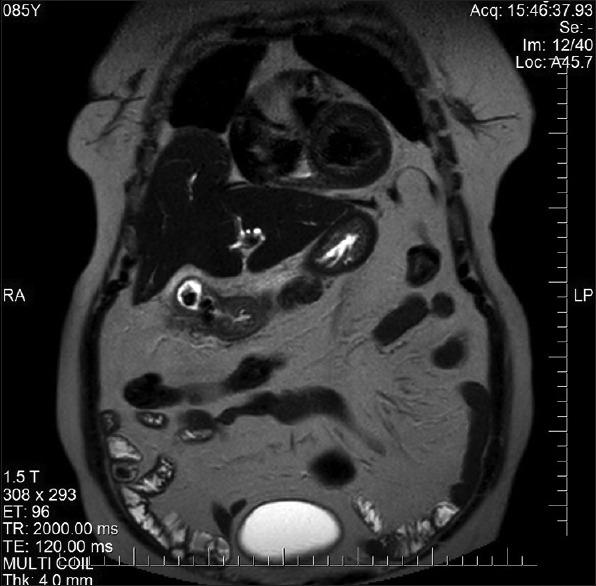

Cholecystoenteric fistulas are rare complications of cholelithiasis, with cholecystogastric fistulas (CGFs) being the rarest. Recommended treatment is surgery; however, select asymptomatic patients can be managed conservatively. The population frequently involved is old age with multiple comorbidities. Open surgery comes with its added morbidities, especially in this subgroup and hence laparoscopic surgery might be beneficial. Sometimes, these fistulas can be incomplete. Here, we describe a case of incomplete CGF managed by laparoscopic cholecystectomy and omental patching along with a brief review of the literature.

胆囊肠瘘是胆石症的罕见并发症,其中胆囊胃瘘(CGF)最为罕见。推荐的治疗方法是手术;然而,部分无症状患者可进行保守治疗。常涉及的人群是老年且伴有多种合并症。开放手术会带来额外的发病风险,尤其是在这一亚组患者中,因此腹腔镜手术可能有益。有时,这些瘘可能是不完全性的。在此,我们描述一例通过腹腔镜胆囊切除术和网膜修补术治疗的不完全性CGF病例,并对相关文献进行简要回顾。